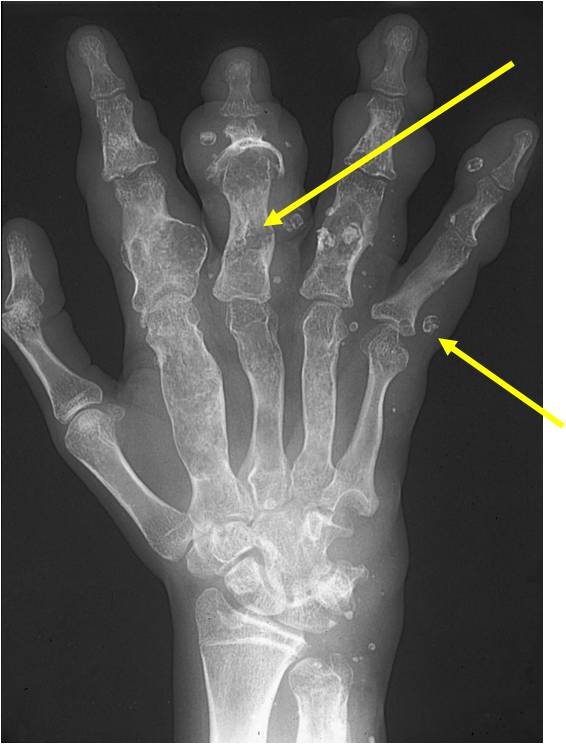

- Localized, radiolucent defect usually with punctate calcifications

- Calcifications are typical but not always present

- Matrix may demonstrate various degrees of calcification

- Calcifications are stippled, punctate, popcorn like calcifications and “Ring and Arc” calcifications

- Cartilage tumors grow in a lobular manner. The perimeters of the lobules undergo

- enchondral ossification that may calcify. If the entire perimeter of the lobule calcifies it appears

- radiographically as a “Ring”. If a portion of the perimeter of a lobule calcifies it forms an “Arc” on

- an X-ray.

- May be located centrally or eccentrically

- Grows eccentrically or concentrically (phalanges)

- Cortex may be scalloped and thinned in the phalanges

Plain X-Ray:

- Geographic lytic lesion

- Central often metaphyseal in long bones

- Can be eccentric also

- Expansile remodeling with thinned cortex

- Chondroid matrix with calcifications in majority of tumors

- Approximately 20% have limited or no calcifications